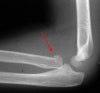

X-ray : 요골두 골절(Radial head fracture)와 동반된 proximal ulnar fracture

보통 AP, lateral, both oblique 즉 4장의 사진을 모두 찍어야 미세한 골절을 찾아내기 수월합니다.

필요시 요골두-소두 촬영을 실시합니다.

잘 보이지 않는 유리체나 골편, 동반된 골절 등의 확인에 CT가 도움을 줍니다.